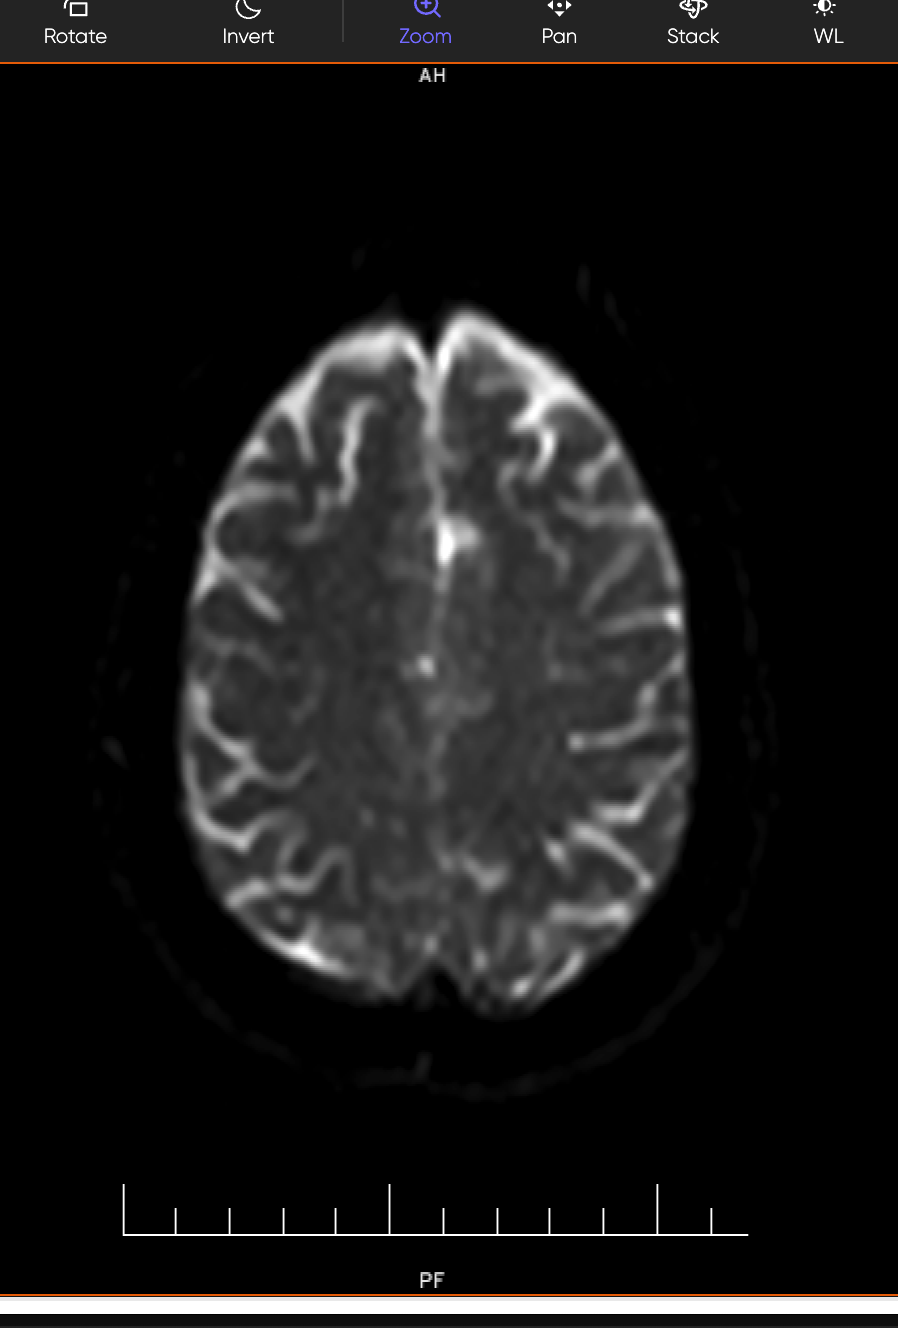

MRI Brain (DWI/ADC — Diffusion Weighted Imaging):

This is the gold-standard sequence for detecting acute stroke — it lights up areas of fresh brain injury within minutes of onset. The MRI confirmed multifocal acute ischemic infarcts in three separate regions:

- Left Corona Radiata — a deep white matter structure involved in motor and cognitive relay pathways

- Right Temporo-Occipital White Matter — associated with visual processing and sensory integration

- Right Occipital Lobe — the brain's primary visual cortex, explaining the patient's visual symptoms

The report also noted "mild chronic ischemic microvascular changes" — evidence that the brain's small vessels had been silently suffering damage for some time, even before this acute event.